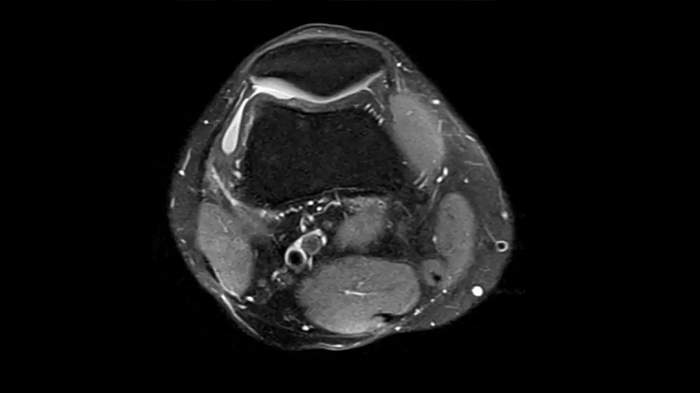

Knee

PD TSE Fat Sat with Deep Resolve and Simultaneous Multi-Slice

For clear imaging of the knee, outstanding fat suppression and performance are possible. Integrating the influence of Deep Resolve with the established Simultaneous Multi-Slice technique.

SMS 2 | Deep Resolve Gain & Sharp

0.4 x 0.4 x 3.0 mm2

TA 2:56 minutes

MAC-ID: 7aaaa0198. Image Credit: Siemens Healthineers

PD TSE Fat Sat with Deep Resolve and Simultaneous Multi-Slice

For clear imaging of the knee, brilliant fat suppression and performance are possible. Integrating the influence of Deep Resolve with the proven Simultaneous Multi-Slice technique.

SMS 2 | Deep Resolve Gain & Sharp

0.3 x 0.3 x 3.0 mm2

TA 2:16 minutes

MAC-ID: 7aaaa0198. Image Credit: Siemens Healthineers

T1 SE

Outstanding T1 imaging of the knee using MAGNETOM Free.Star.

0.3 x 0.3 x 3.0 mm2

TA 2:54 minutes

MAC-ID: 7aaaa0198. Image Credit: Siemens Healthineers

3D MSK Imaging with Compressed Sensing

Knee imaging with T2w SPACE can be expedited using Compressed Sensing to reduce acquisition times, offering high-resolution images for uncompromised knee assessments.

Compressed Sensing 6

0.3 x 0.3 x 0.6 mm2

TA 4:15 minutes

MAC-ID: 7aaaa0175. Image Credit: Siemens Healthineers